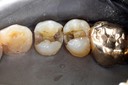

Joe Cha #20 finish